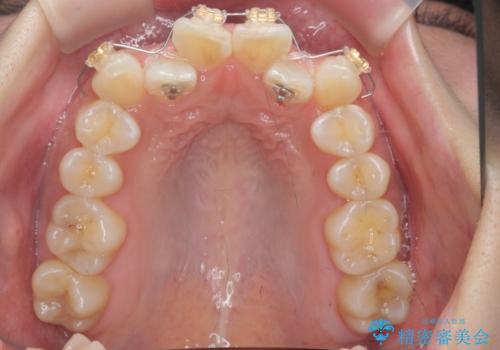

- 前歯のがたつき、受け口を主訴に来院。

上の前歯が二本裏側に入っていました。(反対咬合といいます)

上はワイヤー部分矯正、下はインビザライン(マウスピース)で部分矯正を行いました。

下の前歯を内側に入れる為、一本抜歯しています。